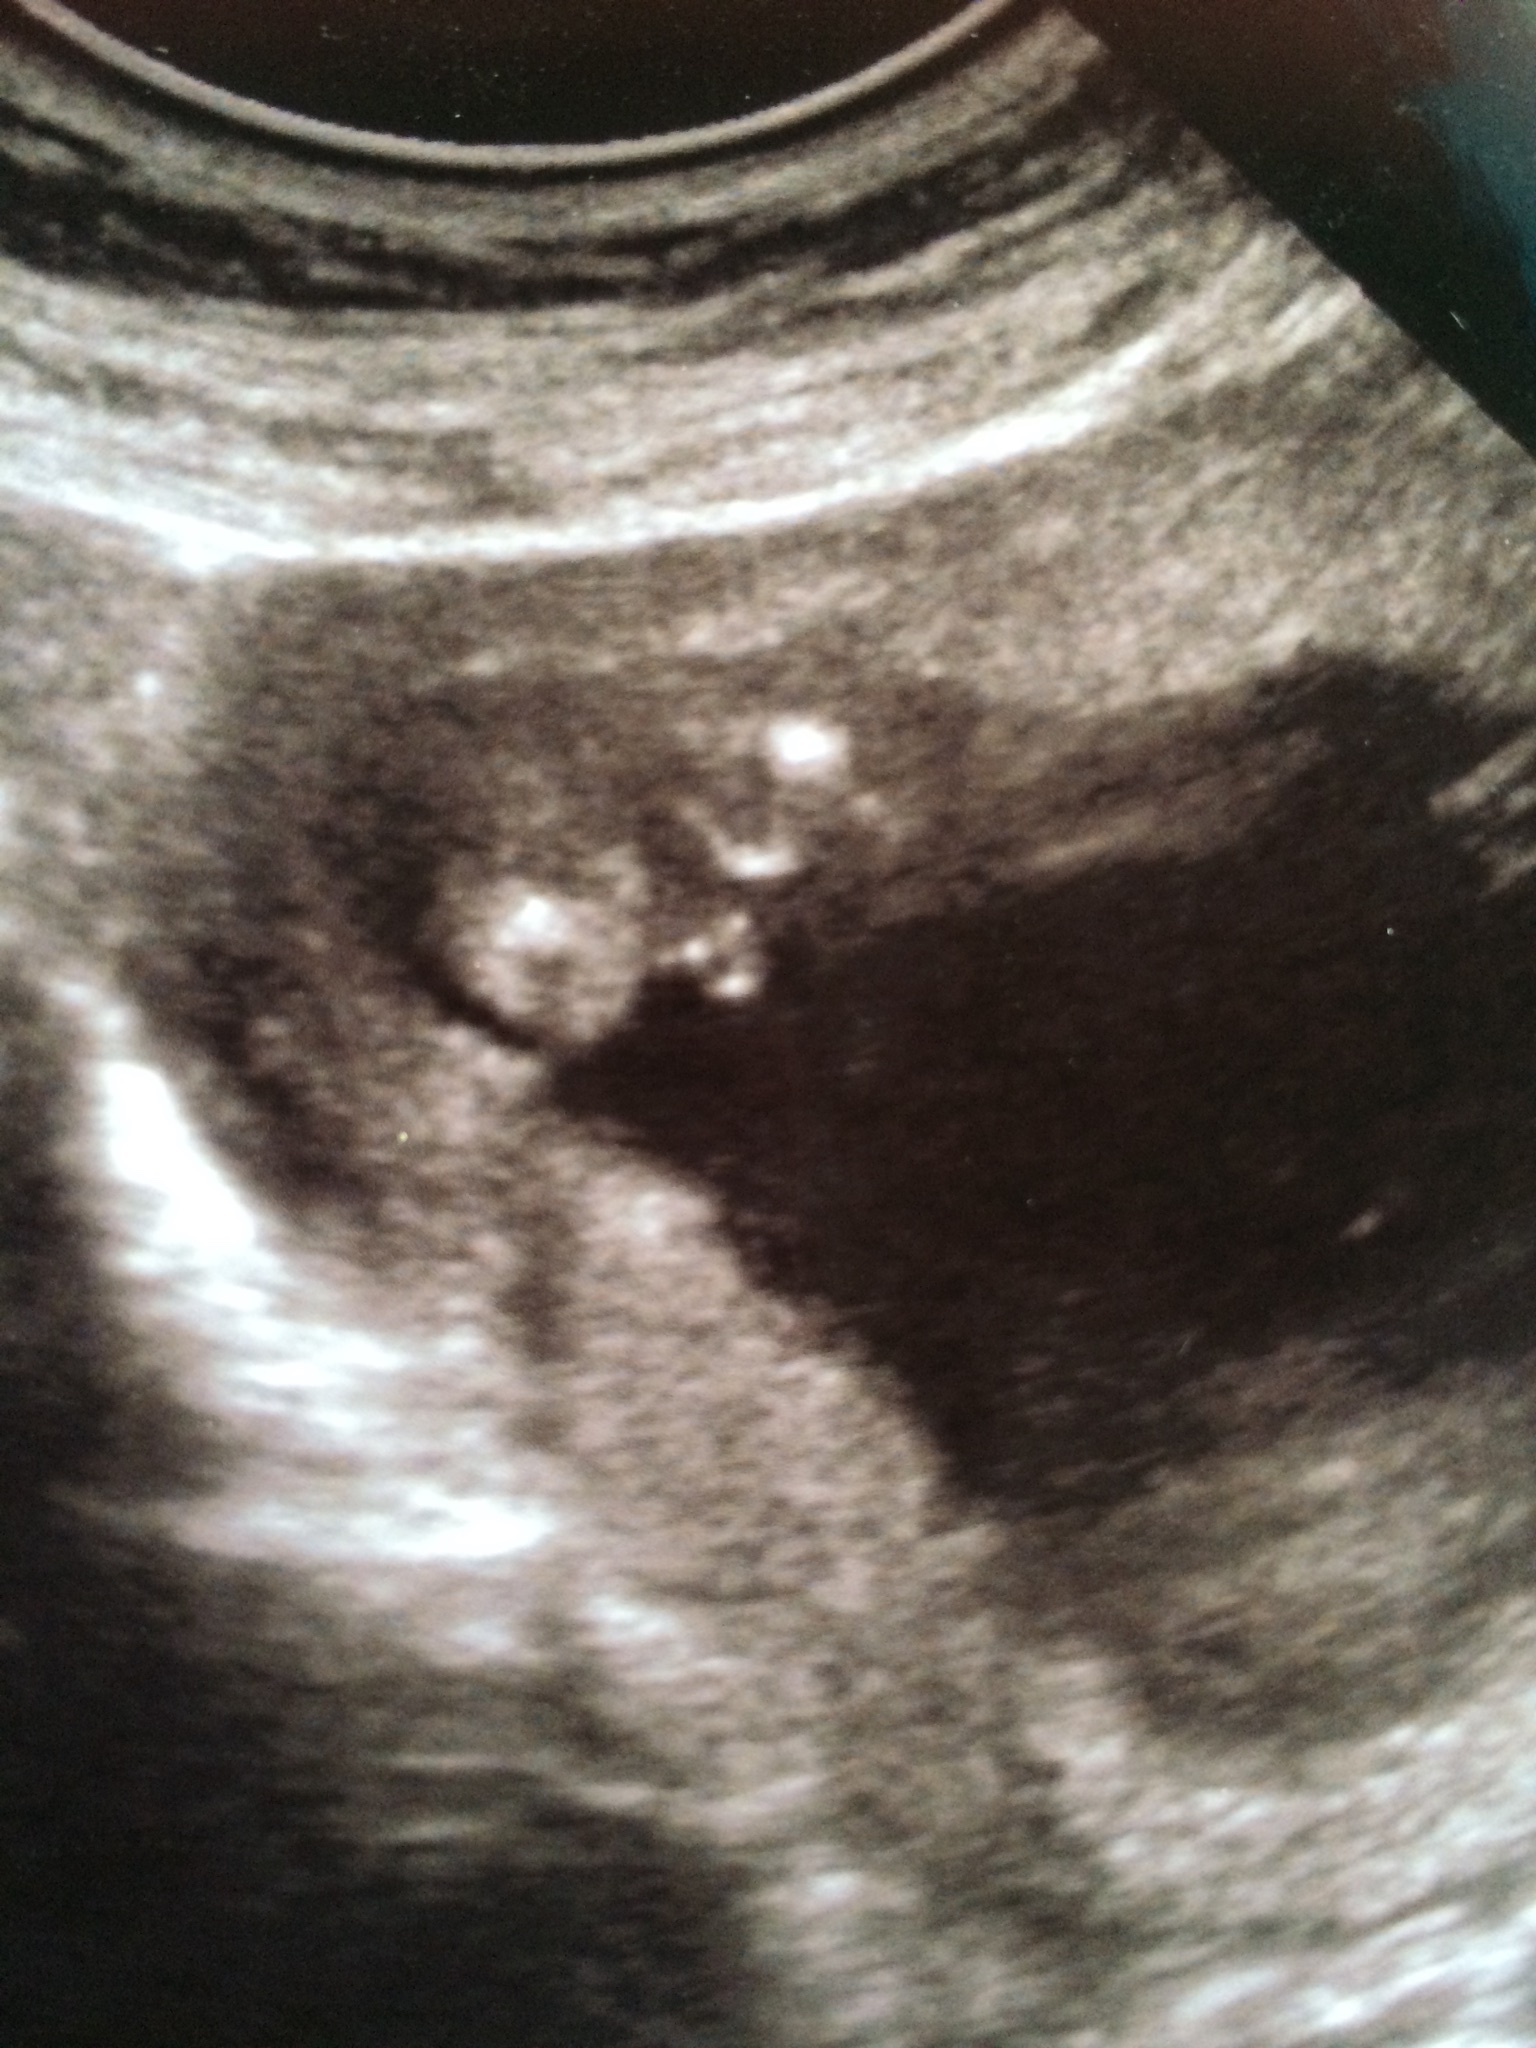

Please, I need to be sure this is a boy 100% before I post my sway. Tech says boy but would like other seasoned opinions. U/S is at 16 wks.

Boy! Congrats!

Looks very boyish to me x